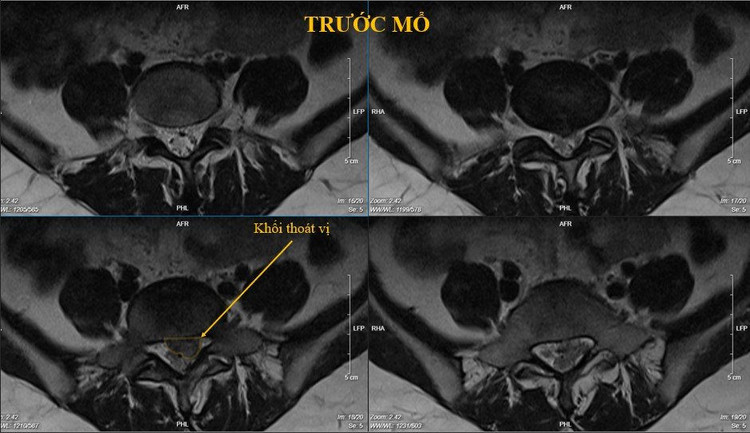

Bệnh nhân nữ 41 tuổi, đau lưng lan dọc mặt sau chân trái theo rễ S1 khoảng 1 năm nay, gần đây đau dữ dội, không thể đứng thẳng được, đi lại rất khó khăn.

Bệnh nhân đã được điều trị rất nhiều phương pháp nhưng không cải thiện, trên MRI có khối thoát vị L5S1 bên trái có di trú xuống dưới, chèn ép rất nhiều vào ống sống. Bệnh nhân đã được phẫu thuật nội soi lấy khối thoát vị. Sau mổ bệnh nhân hết đau lưng, đi lại bình thường.